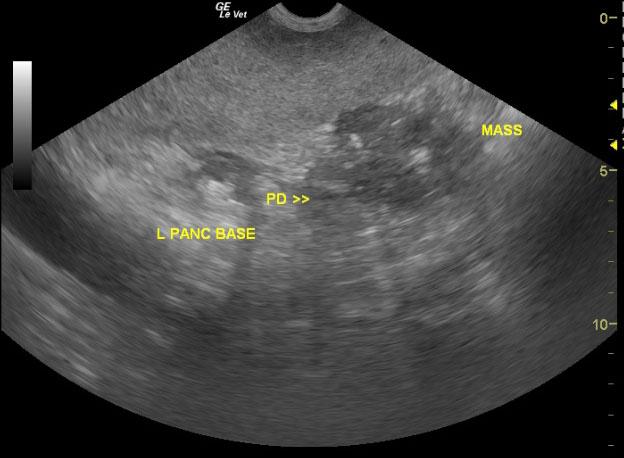

The pancreas was largely normal with minor age related changes in the right limb and right pancreatic base. However, the left pancreatic base opened up into a large 10+ cm mineralizing mass. This is consistent with pancreatic carcinoma. Some omental adhesions were noted in the mid-abdomen. The mesenteric root was not visualized given that it was obscured by the mass.

uMAsswithlabelsPowermass